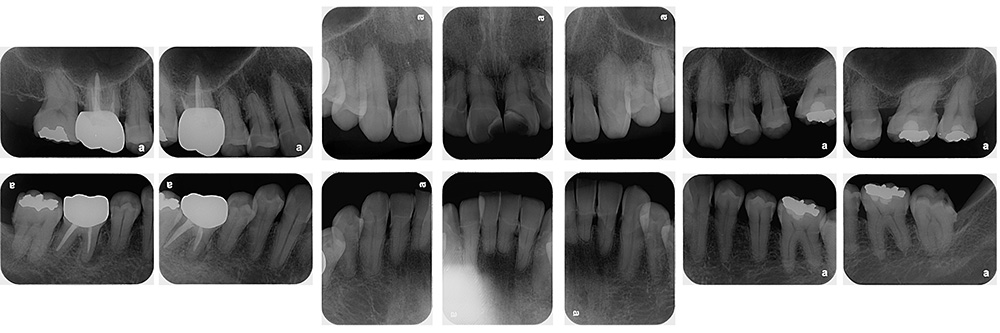

世代・性別

60代男性

主訴

歯ブラシで出血するので見てほしい

治療内容

ブラッシング指導、歯周基本治療、虫歯治療、根管治療、補綴治療

治療期間

6ヶ月

治療費

保険適応内

治療のリスク

治療後にしみる・痛みが出ることがある